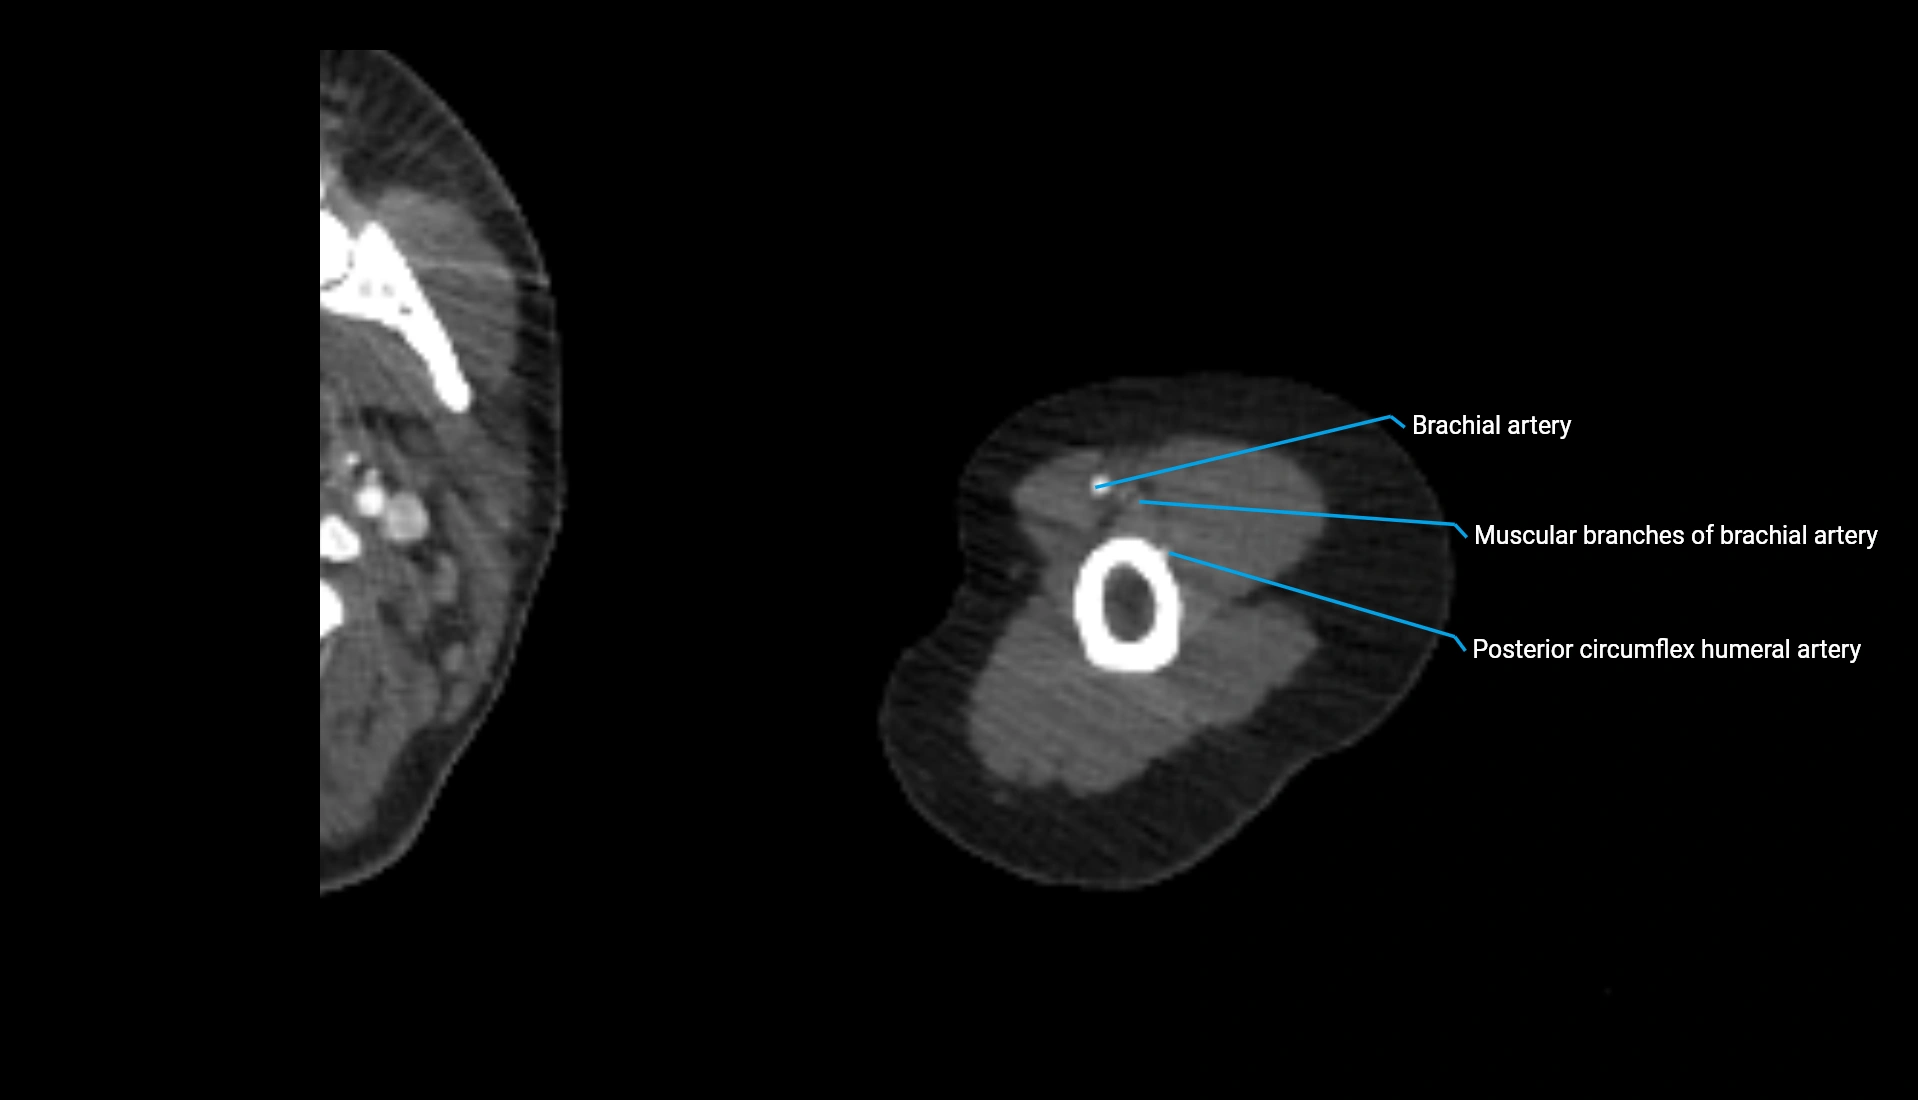

CT Appearance

Non-Contrast CT:

• Cortex: High-density, sharply defined

• Subchondral bone: Dense cancellous matrix

• Articular surface: Smooth concave contour articulating with the capitellum

• Excellent for evaluating bone integrity, alignment, and subtle fractures